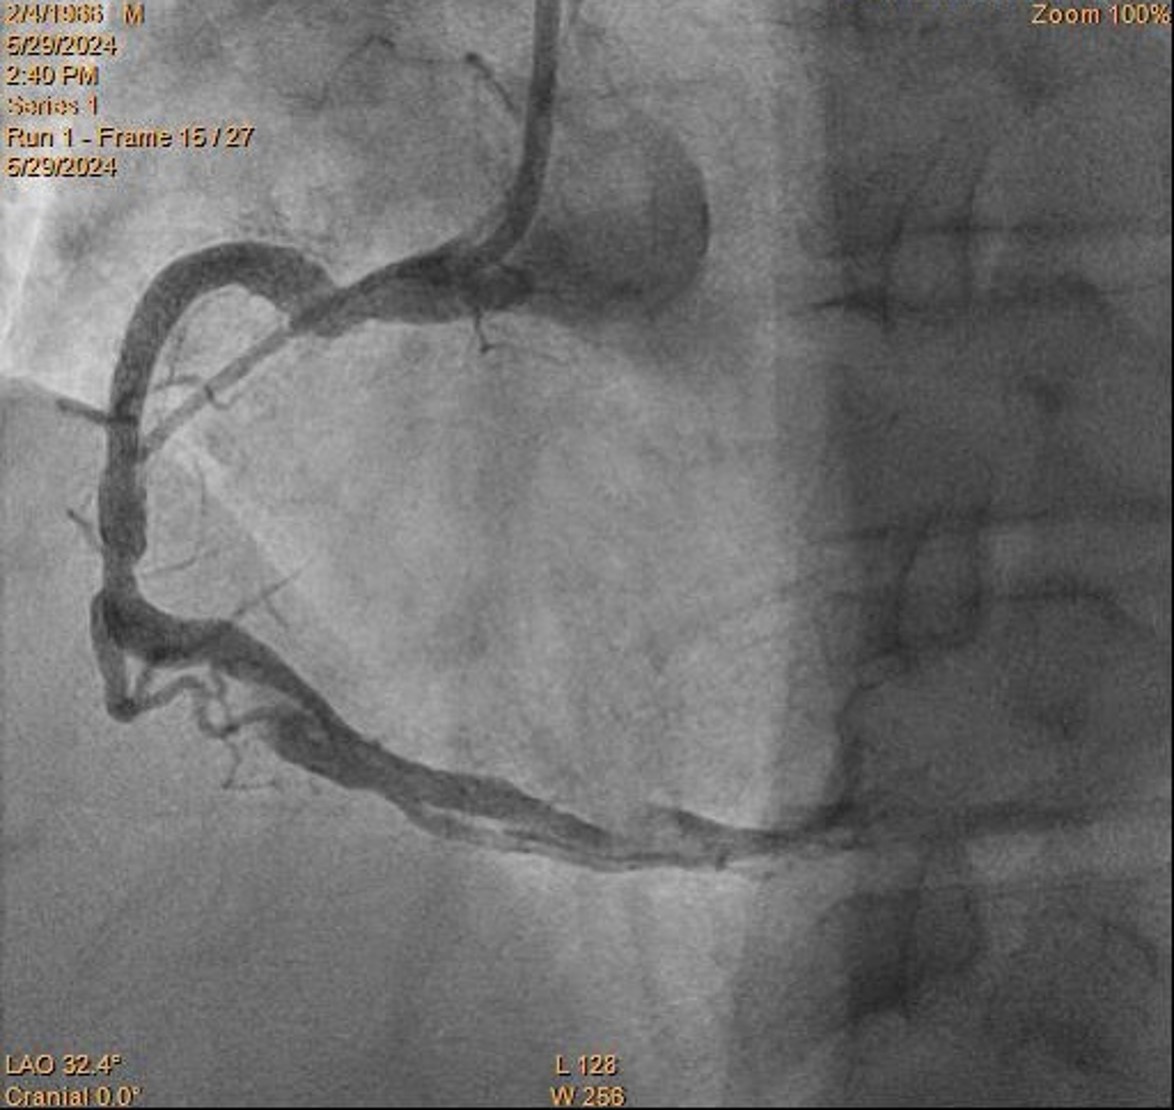

Coronary angiogram: LMS: normalLAD: diffuse disease up to 40% stenosis over p-mLADLCX: minor diseaseRCA: pRCA total occlusion with ? flapIRA = RCAPlan: PPCI to RCA

RCA is engaged with JR4.

Initially coronary dissection is suspected as pathology due to unusual angio appearance.

Difficult wiring is noted partly due to uncertain pathology. Eventually RCA is successful wired with Sion Black to distal. IVUS then confirmed giant pRCA coronary aneurysm with a large thrombus.

Size of aneurysm exceeded the US scan limits for measurement and angiographically > 10 mm. Multiple dilatation is attempted with 2.0 and 3.0 balloons, followed by clot aspiration with CAT Rx. . Despite of that, RCA remains in totally occluded with TIMI 0 flow.

This presentation shows a case of inferior STEMI with very big RCA aneurysm and thrombus formation inside.

Despite balloon dilatation and thrombectomy, flow is yet to be restored. Flow is restored after stenting. IVUS shows the aneurysm is so big beyond the limit of the machine, with thrombus inside. Stent landed on distal edge of aneurysm. Restudy coro showed TIMI III flow. Difficult rewiring requires use of crusade and 2nd wire. IVUS shows stent malapposed. No available coronary stent is big enough to cover the aneurysm. Reviewed in team meeting, it is decided for lifelong anticoagulation.